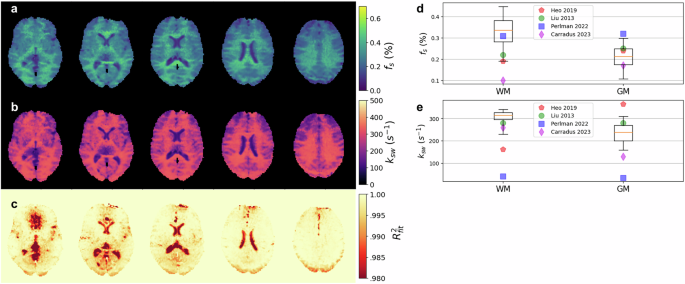

Quantitative semisolid-MT and amide proton exchange parameter maps derived from a representative healthy volunteer are presented in Fig. 3 and Fig. 4, respectively. The resulting proton volume fractions and exchange rates were in agreement with the literature (although the large variability in previous reports is noted; see Fig. 3d, e and Fig. 4d, e). The mean values obtained for white/gray matter (WM/GM) were: fss = 13.09 ± 3.44(%), kssw = 34.7 ± 7.8(s−1), fs = 0.33 ± 0.08(%), ksw = 305.1 ± 34.0(s−1) for white matter and fss = 6.28 ± 1.88(%), kssw = 44.2 ± 7.5(s−1), fs = 0.21 ± 0.06(%), ksw = 235.9 ± 46.0(s−1) for gray matter.

Results of neural Bloch-McConnell fitting (NBMF)-based quantification of the APT-related tissue parameters in a human brain scanned with a pulsed Chemical Exchange Saturation Transfer Magnetic Resonance Fingerprinting (CEST-MRF) protocol. Representative reconstructed parameter maps of the amide proton volume fraction (a) and proton exchange rate (b), alongside a fidelity estimation (c) of the data-model agreement, computed as R2 = 1-NMSE (normalized mean square error). d, e Statistical analysis of the resulting proton exchange parameter values across the brain white matter and gray matter (WM/GM) regions of interest (box-plots, n = 47442/64611 voxels, respectively), compared to literature (colored markers)12,45,91,92. In the boxplots, the central horizontal lines represent median values, box size represents the two central (2nd, 3rd) quartiles, the whiskers represent the 90 central percentiles, and outliers are omitted.